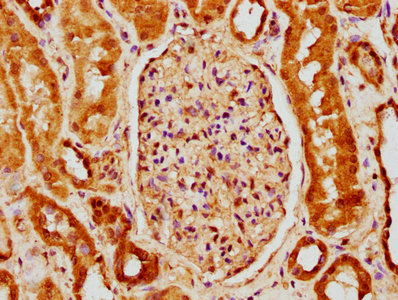

IHC image of CSB-PA884627LA01HU diluted at 1:150 and staining in paraffin-embedded human kidney tissue performed on a Leica BondTM system. After dewaxing and hydration, antigen retrieval was mediated by high pressure in a citrate buffer (pH 6.0). Section was blocked with 10% normal goat serum 30min at RT. Then primary antibody (1% BSA) was incubated at 4°C overnight. The primary is detected by a biotinylated secondary antibody and visualized using an HRP conjugated SP system.